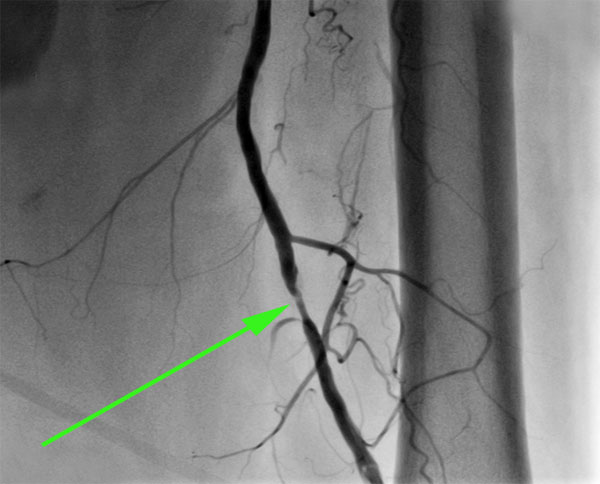

Анатомия коронарных артерий: КТ-изображения

Раздел: Снимки успеха